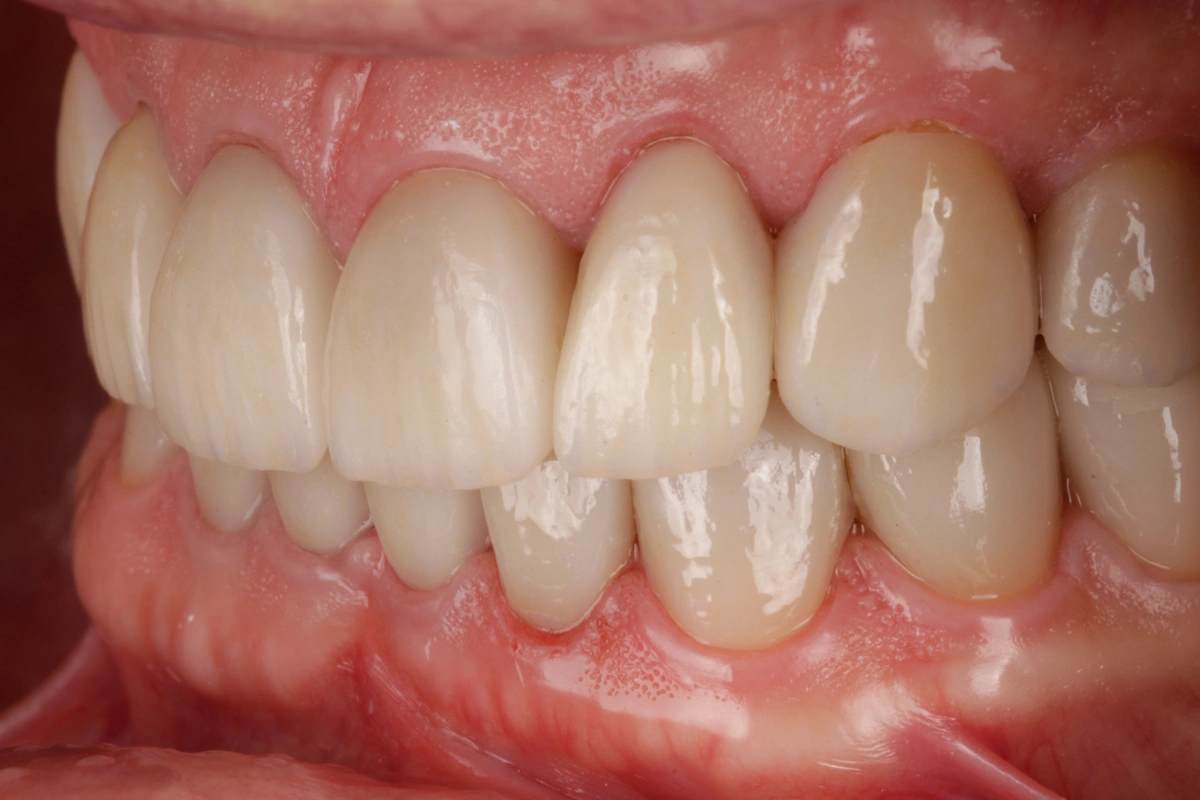

Tras realizar un estudio exhaustivo optamos por una rehabilitación completa con coronas, carillas e incrustaciones en disilicato de litio. Realizamos una prueba previa a la preparación de los dientes para establecer la longitud de los dientes definitivos.

Al finalizar el tratamiento, protegemos con una férula nocturna tipo Michigan.